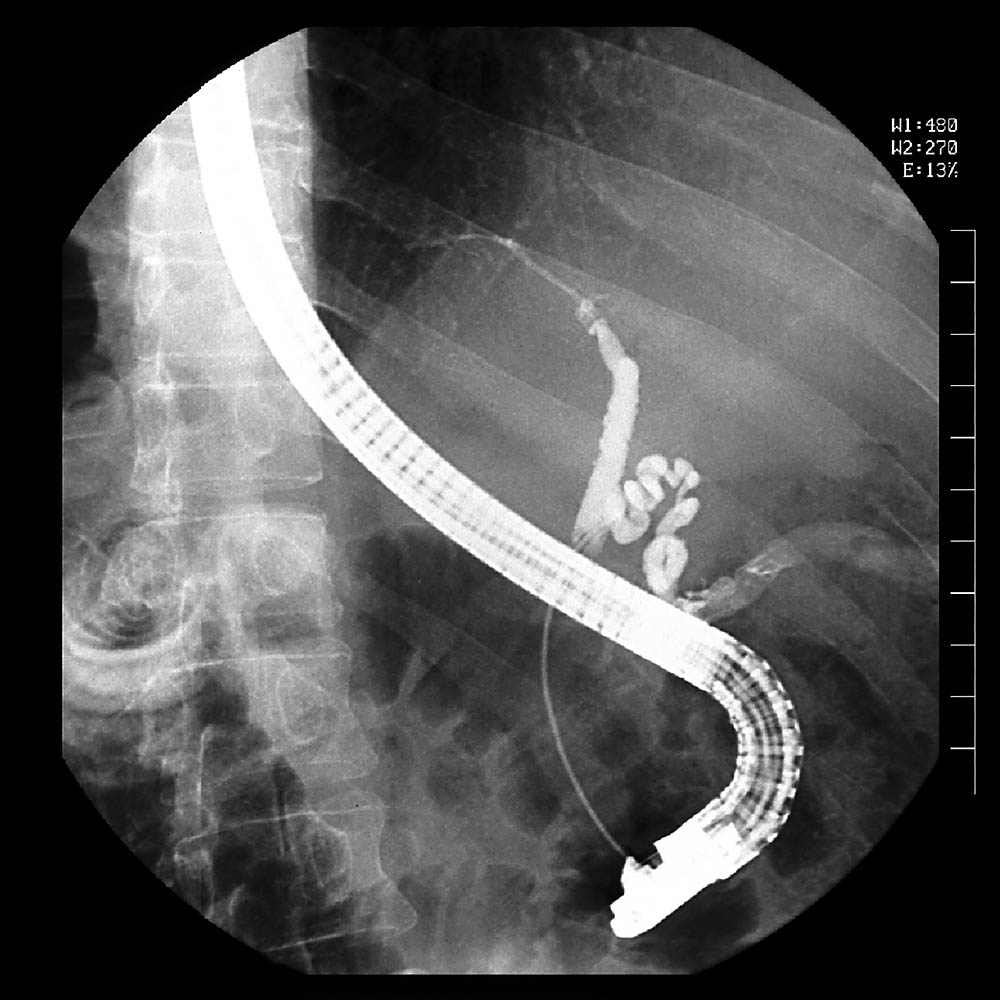

내시경 역행 췌담관 조영술 (출처 : 위키미디어)

쓸개돌(Gallstone)이 췌관을 막는 경우와 같이 근본원인이 췌관에 문제로 인한 것이라면 내시경 역행 췌담관 조영술(ERCP)을 시행해서 치료할 수 있습니다. 술(알코올)이 원인이라면 궁극적으로는 금주가 필수입니다. 고중성지방혈증(Hypertriglycemia)을 해결하는 체중조절, 식단조절, 약물치료 등도 원인 치료입니다.